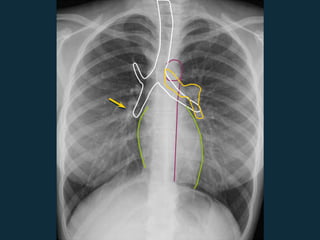

Basic CXR Anatomy

Incidência em PA e Perfil

 Coração

 Aorta

 Artérias

pulmonares

 Vias aéreas

 Arco aórtico

 Artéria pulmonar

direita

esquerda

 Traquéia &

brônquios